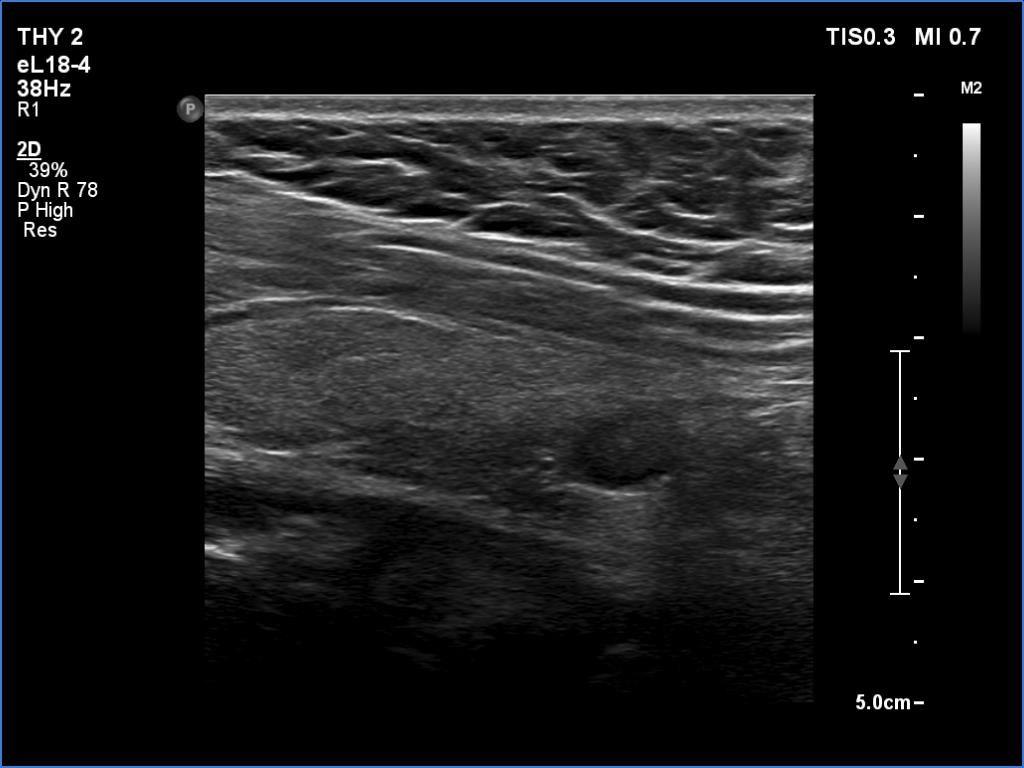

Ultrasonography. The thyroid was echonormal. Using higher frequency three discrete hypoechoic lesions were found, one in the middle dorsal part of the right lobe, one in the middle and a third one in the lower dorsal part of the left lobe. By decreasing the frequency, the presence of only the third one could be confirmed.

FNA of the nodule in the lower dorsal part of the left lobe resulted in benign colloid goiter.

Comment. It is a rule that larger the distance from the probe worse the permeability of ultrasound wave. This can lead in certain patients (overweighted ones or frequently in men) that the dorsal part of the thyroid lobe can deceptively look darker, i.e. hypoechoic. If we have any doubt, by lowering the frequency i.e. increasing the penetrance, the real situation can be much better to judge.

This happened in this patient. If we would trust the pattern gained by higher frequency settings, we would falsely diagnose at least one additional nodule.